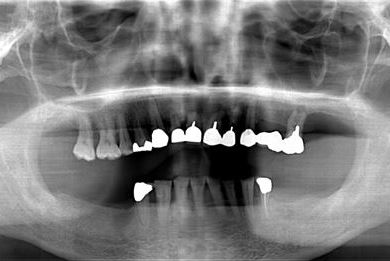

インプラントの症例写真 IMPLANT

骨再生スピードインプラント治療+セラミック治療

| 性別/年齢 | 男性 / 53歳 | ||||||||||||||||||||||||||||||||

| 主訴 | インプラント治療の相談。 | ||||||||||||||||||||||||||||||||

| 治療方針 | 上前歯部は、抜歯と同時にインプラントを埋入し、治療期間を短縮する。左上奥は、ソケットリフトにて上顎洞を拳上し、インプラント治療を可能にする。 | ||||||||||||||||||||||||||||||||

| 治療内容 | インプラント4本(ソケットリフト・抜歯即日)、テンポラリーインプラント2本、メタルボンドクラウン9本 | ||||||||||||||||||||||||||||||||

| 総治療費 | 2,025,975円 | ||||||||||||||||||||||||||||||||

| 治療期間 | 1年9ヶ月 |